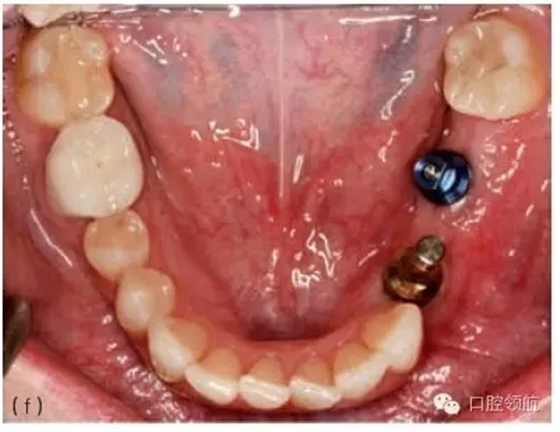

圖10.1 (a)個(gè)性化基臺(tái)連接在種植體上的牙合面觀。螺絲的長(zhǎng)軸對(duì)應(yīng)的是種植體的長(zhǎng)軸,螺絲的長(zhǎng)軸傾斜,基臺(tái)螺絲孔通頰側(cè)面。(b)成品基臺(tái)的頰面觀,螺絲的入口清晰可見(jiàn)。(c)上頜種植體的轉(zhuǎn)移替代體,反映種植體頰側(cè)傾斜的角度。(d)使用個(gè)性化鑄造基臺(tái)能獲得良好的美學(xué)效果。(e)轉(zhuǎn)移替代體顯示種植體的方向不平衡。(f)轉(zhuǎn)移替代體在口內(nèi)頜面觀,如圖可見(jiàn)遠(yuǎn)中種植體舌傾。(g)制作診斷蠟型以確定最終修復(fù)體的外形。(h)個(gè)性化基臺(tái)的代型,遠(yuǎn)中種植體的螺絲入口位于近中舌側(cè)位。固定局部義齒將會(huì)粘結(jié)于個(gè)性化基臺(tái)上。